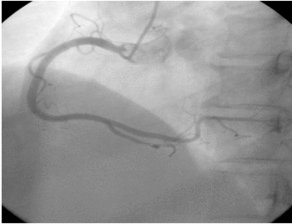

冠動脈造影検査は、大腿動脈の位置から針を刺し、冠動脈の位置までチューブを通し、ヨード造影剤を打ち込んで冠動脈を映し出し、冠動脈の先天性疾患、アテローム性動脈硬化症、動脈瘤、動脈奇形などを診断するもので、その多くは内腔の狭窄をもたらすアテローム性動脈硬化症である。狭窄の程度を評価することができ、心筋梗塞を伴う重度の狭窄の場合は、治療目的で狭窄した内腔を広げて血流を回復させるためにステントを直接挿入することができる。

心血管造影は冠動脈造影を指し、一般的なプロセスは、最初の検査者の橈骨動脈または大腿動脈で小さな開口部をカットし、細いカテーテルは、切開から挿入される動脈の方向に沿って冠動脈に深くされており、その後、冠動脈画像は、冠動脈疾患とその枝の冠動脈疾患の部位と程度の狭窄について明確にすることができるように、造影剤に注入され、冠動脈疾患の診断です。「ゴールドスタンダード」である。以下、3つの問題を合わせて理解する:

心臓造影の基本的な手順は、橈骨動脈(手首)または大腿動脈(太ももの付け根)に穿刺してカテーテルを留置し、ガイドワイヤーを使ってカテーテルを心臓や心臓周辺の重要な血管(大動脈、冠動脈)に逆行性に誘導し、そこに造影剤を注入して、X線の効果で心室や心臓周辺の重要な血管の構造を見えるようにする。

心臓造影検査は冠動脈造影検査としても知られ、心臓専門医が行う最も一般的な検査の一つであり、冠動脈疾患の診断を確定するためのゴールドスタンダードです!心エコー図検査とは何ですか?心電図検査は橈骨動脈、大腿動脈、動脈などの動脈アプローチを使って行われます。動脈アプローチでは、冠動脈の開口部にカテーテルを送り、そこから造影剤を注入して冠動脈をX線で可視化します。